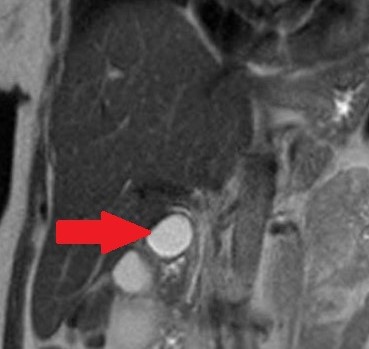

Polycystic liver disease. Red arrow. Infected hepatic cyst (Courtesy Dr. V. Penopoulos)